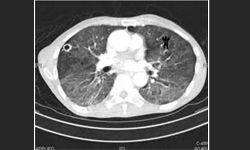

Increasing knowledge of the diverse pathologic and molecular phenotypes in non-small cell lung cancer (NSCLC) has driven a more complex treatment algorithm in recent years.

As with many cancers, early detection (before the onset of symptoms) offers the possibility for less expensive treatment and better outcomes in patients with non-small cell lung cancer (NSCLC).

Early diagnosis of lung cancer is crucial, because surgery is curative only in the early stages. However, by the time most patients experience symptoms, the cancer has already progressed beyond the point of successful surgery.